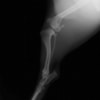

術前左後肢側面像

術後左後肢側面像

本症例は、走った後に左後肢を挙上していることを主訴に来院されました。触診時に左膝関節のクリック音を聴取、レントゲン検査にて左脛骨の前方変位が認められました。術中に、前十字靱帯の断裂及び内側半月板の損傷、内側の軟部組織の顕著な腫脹を確認。半月板切除、TPLOを実施しました。周囲組織への炎症の波及もあったため回復に時間を要しておりますが、徐々に跛行頻度は減少傾向にあり、現在も経過観察中です。術前に約29°あったTPAは術後に約10°まで矯正されました。

手術前後のTPA(脛骨高平部の角度)を測定しています。

約29°から約10°へ矯正されています。